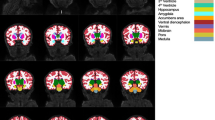

Gray matter VBM analysis of T1 data

Compared to the full-term controls, the preterm group had decreased gray matter densities in the thalamus bilaterally, the left caudate and bilaterally in the hippocampus as well as in the posterior division of the right middle temporal gyrus, parts of the lingual gyrus and the left posterior part of the cerebellum.

Increased gray matter densities were found bilaterally in the frontal cortices, in the right temporo-occipital part of the middle temporal gyrus, the right occipital cortex and bilaterally in the intracalcarine cortex and the anterior part of the cingulate gyrus. The most prominent clusters of altered gray matter densities showed a pattern of bilaterality (Fig. 3 and Table 2).

In the premature group, there was no correlation between gestational age and gray matter density. No difference in gray matter densities was observed among preterm-born children in relation to antenatal steroids. The preterm-born children with neonatal IVH showed decreased gray matter in a small region in the temporo-occipital cortex, as compared to those without IVH.